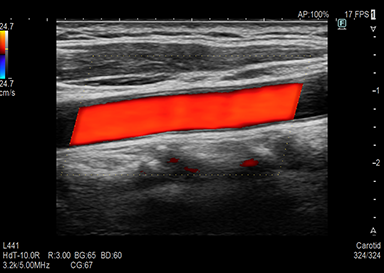

頸部(動静脈・甲状腺)、心臓、腹部(肝臓・胆のう・膵臓・脾臓・腎臓・膀胱・腹部大動脈等)、下肢(動脈・静脈)等が観察できる検査です。

超音波機器について

超音波検査では機械の性能が画質を決定します。性能の良い超音波機器での検査ではより詳細な情報が得られます。